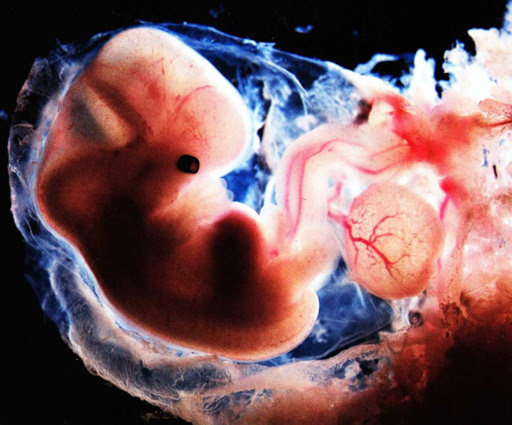

Không thể phủ nhận được vai trò quan trọng của siêu âm trong việc theo dõi sự phát triển của thai nhi. Hiện nay, ngoài siêu âm 2D còn có thêm các kỹ thuật siêu âm màu tiên tiến, giúp phát hiện sớm các dị tật bất thường ở trẻ, nhờ đó mà đưa ra những phương án xử lý kịp thời, an toàn cho cả mẹ và c...

Sàng lọc trước sinh là gì, nên thực hiện vào thời điểm nào?

Là bậc làm cha mẹ, ai cũng mong muốn con yêu của mình chào đời khỏe mạnh. Vì thế, sàng lọc trước sinh là việc làm cần thiết giúp bé yêu chào đời khỏe mạnh, an toàn. Vậy sàng lọc trước sinh là gì? Phương pháp này có ý nghĩa gì cho mẹ và bé? Hãy cùng MEDLATEC giải đáp các thắc mắc qua bài viết sau...